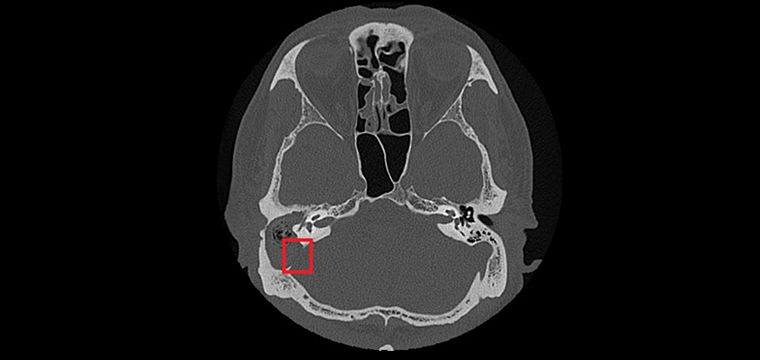

▲紅框處可見與後顱窩相隔的骨板被膽脂瘤侵蝕。(圖/台北慈濟醫院提供)

【NOW健康 楊芷晴/新北報導】75歲張先生右耳曾罹患慢性中耳炎並合併耳聾。近日右耳出現耳痛、耳脹並伴隨膿性分泌物,原先於診所治療未見改善,轉至台北慈濟醫院就診時,檢查發現外耳道嚴重紅腫狹窄,內部堆積大量碎屑及膿液。台北慈濟醫院耳鼻喉科鄭靜雯醫師在進行局部清理及藥物治療後,症狀仍未明顯改善,後續更出現右側顏面神經麻痺。經顳骨電腦斷層檢查確認為慢性中耳炎併發膽脂瘤,且病灶已侵蝕顱底骨質,需安排住院治療。

由於膽脂瘤多發生在中耳或接近顱底的位置,一旦形成,可能影響聽力與神經功能,其分泌物亦容易滋生細菌,導致反覆感染;若未及時治療,可能引發暈眩,甚至因鄰近顱內而造成腦膜炎、腦炎或腦膿瘍。目前,手術切除是膽脂瘤根治的唯一方法,術前需以顳骨電腦斷層檢查評估膽脂瘤範圍及侵蝕程度;手術方式依病灶大小、位置,可能採耳內微創、耳前或耳後切開術,徹底清除膽脂瘤並重建受損結構。急性發炎期則需輔以抗生素控制感染,術後追蹤可降低復發風險,但膽脂瘤若已侵蝕骨質,仍需長期觀察。